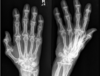

**Colles - ‘dinner fork type deformity’** Features of the injury 1. Transverse fracture of the radius 2. 1 inch proximal to the radio-carpal joint 3. Dorsal displacement and angulation of the distal radius

Colles fracture ## Footnote Typically FOOSH forwards Extra-articular radial # with dorsal (posterior / back of hand) angulation and displacement